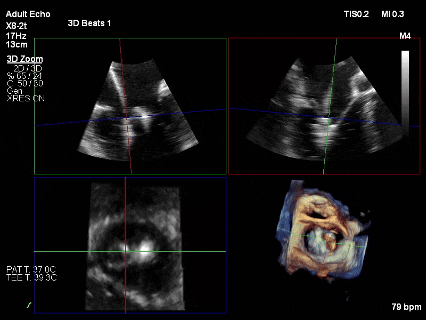

术后影像

最终结果3D-Zoom-color显示组织桥稳定,原脱垂区域前后叶对合部分的脱垂已消除,反流降至1+以下

夹子释放Bi-com切面显示残余反流情况

肺静脉收缩期逆流消失,频谱形态基本恢复正常

术后2D TTE:

术后TTE可见二尖瓣微量-轻度反流,三尖瓣反流明显改善降至中度